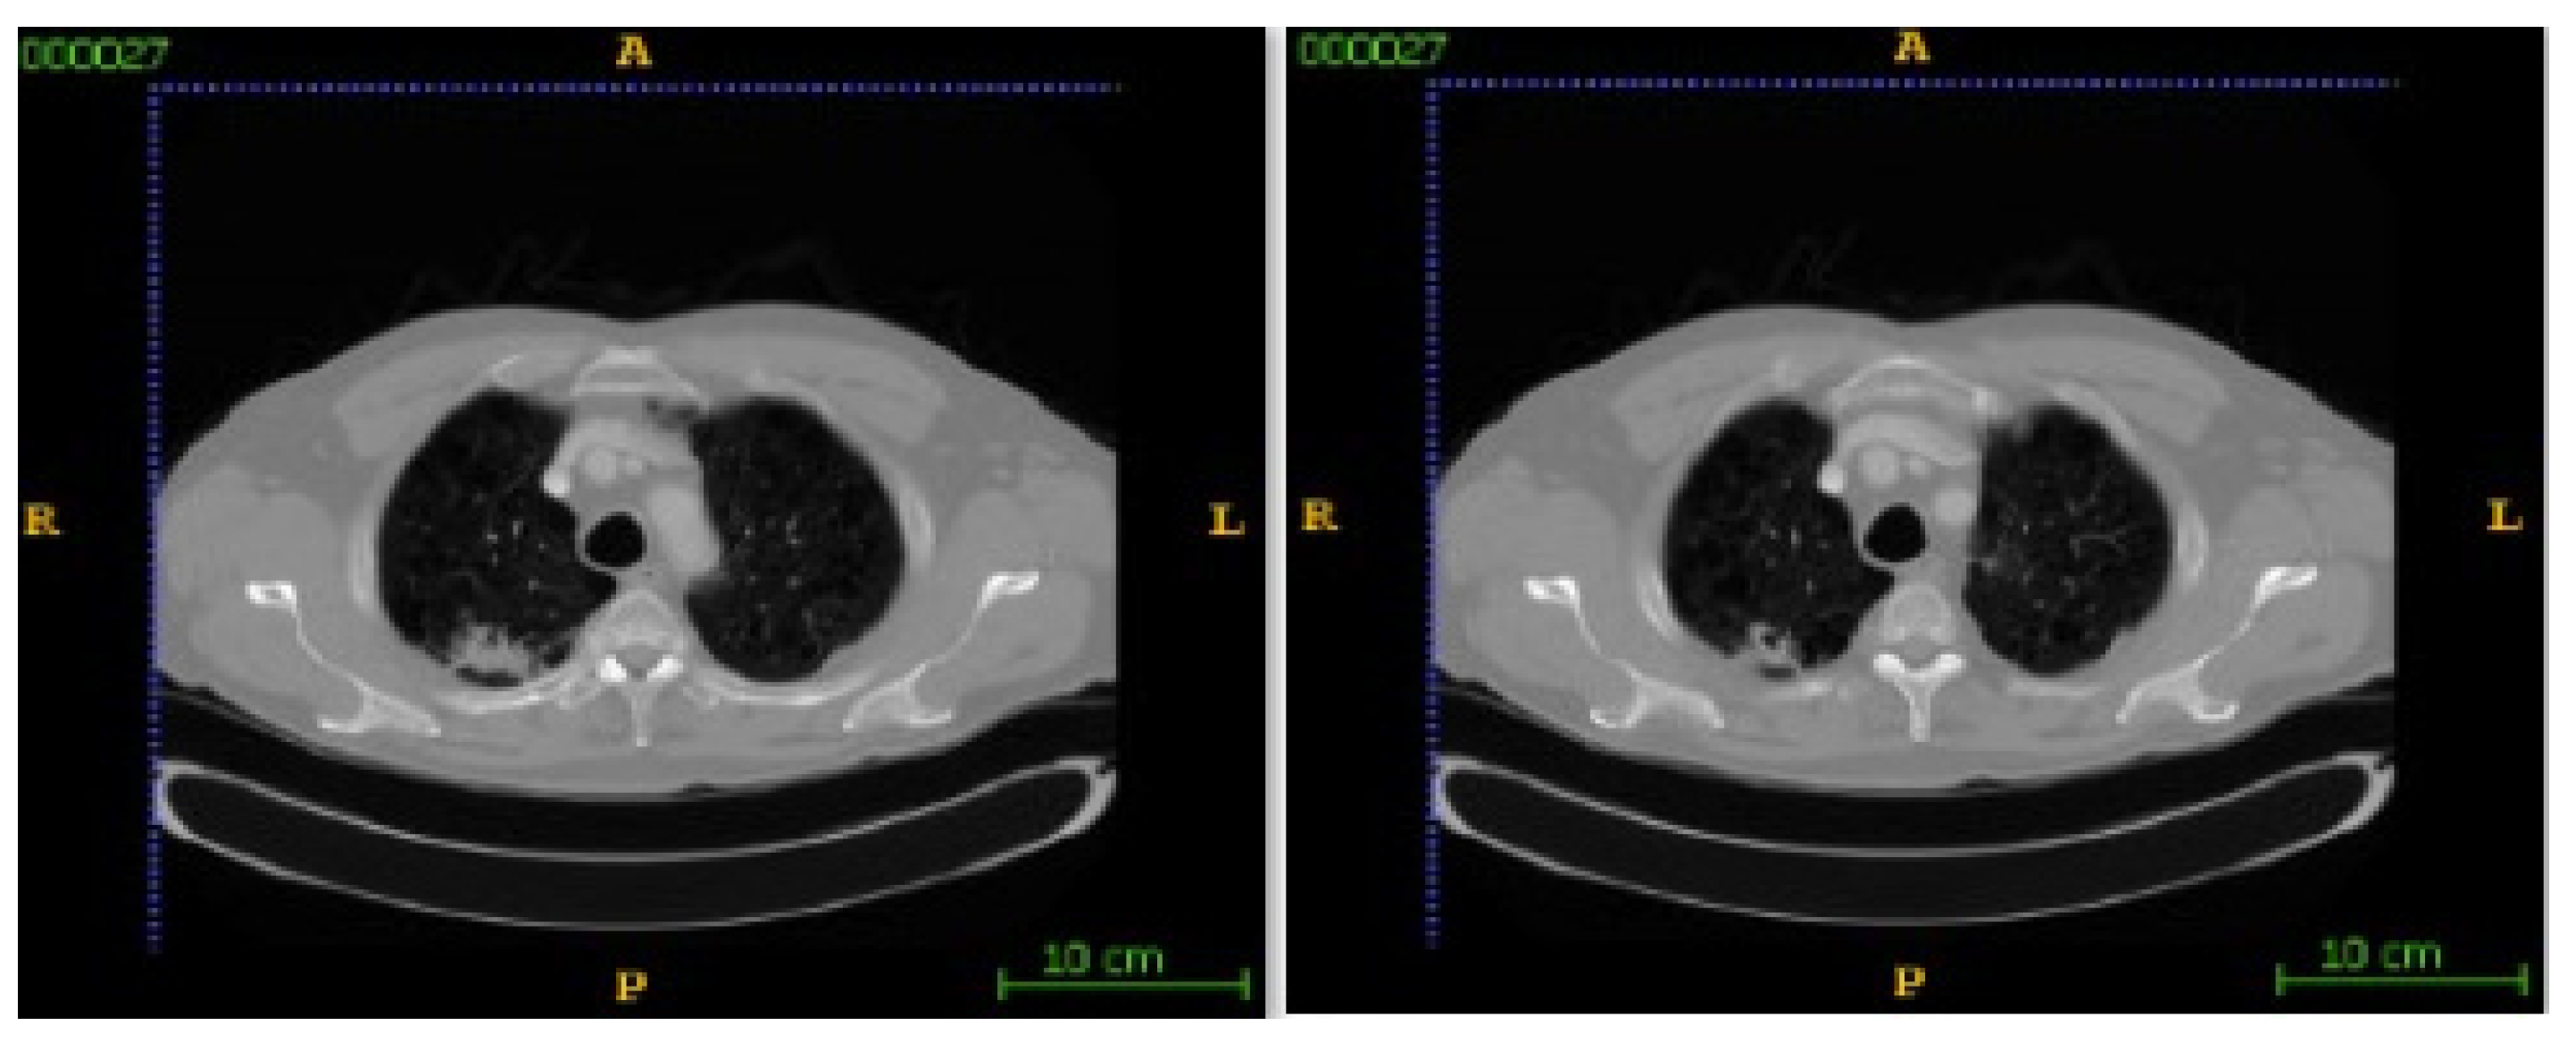

In this section, the segmentation results of the RW-ensemble are visualized for distinct types of nodules. The results for three different types of nodules from the LCT-D dataset are demonstrated: solid nodules, juxta-vascular, and pleural nodules. To improve clarity, each case is visualized through CT slices and the corresponding RW-ensemble segmented outputs, organized by nodule type and patient ID. Figure 6 and Figure 7 represent the solid nodule and its respective RW-E segmented images in grey-scale for patient R_0108. The juxta-vascular nodules of patient R_0052 are shown in Figure 8, and the corresponding RW-E segmented output images are illustrated in Figure 9. Juxta-pleural nodules, which are challenging due to their attachment to the lung wall, are illustrated in Figure 10 and Figure 11 for patient QIN_LSC_0064.

Figure 10. CT slices showing juxta-pleural nodules (Patient QIN_LSC_0064).

Bioengineering 12 00576 g010